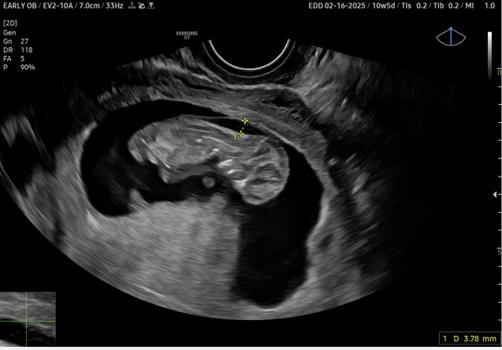

The figure demonstrates between +...+ a nuchal translucency measurement

BRIEFING: This month’s reviewed test is nuchal translucency testing by ultrasound in early pregnancy. It is used as a screening test for certain chromosomal and morphological abnormalities a pregnancy can suffer from and demonstrates well the difference between a screening and diagnostic test.

Nuchal translucency (NT) testing is an early ultrasound test that assesses the risk of chromosomal abnormalities in a pregnancy, mostly Down’s syndrome (also called trisomy 21). NT refers to a physiological accumulation of fluid at the back of a fetus’s neck, detectable in all fetuses during the first trimester of pregnancy (see the figure above). An increased NT measurement can indicate various fetal pathological conditions, including congenital cardiac anomalies, chromosomal abnormalities, and genetic disorders.

To correctly perform the test, the ultrasound image must be a mid-sagittal view. This means the ultrasound image should be a clear, longitudinal view of the fetus, showing a profile that includes the neck, nasal bone and the palate. The fetus’s head should be in a neutral position, not tilted too far back (hyperextended) or too far forward (flexed). Moreover, the head should be in line with the spine.

The sonographer then measures the thickness of the nuchal translucency. This measurement is done by placing calipers on the ultrasound image to measure the maximum thickness of the translucent area. At 11 weeks, a normal NT measurement should not exceed 2 mm. At 13 weeks and 6 days, a normal measurement is up to 2.8 mm, though some practices consider normal to be up to 3.5 mm.